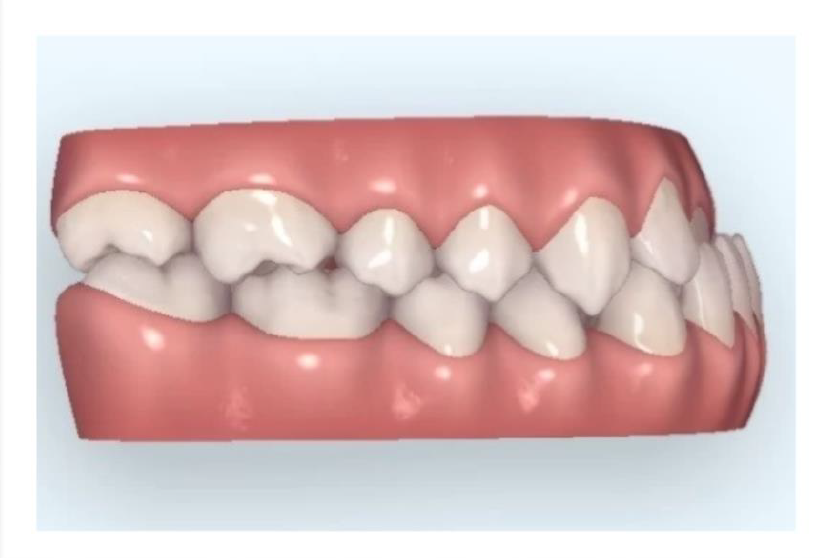

Problemy w prawidłowym (fizjologicznym) przepływem powietrza przez górne drogi oddechowe stwarzają zagrożenie dla zgryzu. Ograniczenia przepływu przez nos (alergiczny obrzęk śluzówki, skrzywienie przegrody nosowej, polipy przerost nozdrzy tylnych i inne) najczęściej zmuszają do otwarcia ust i oddychania torem ustnym. Nie tylko powoduje to dostanie się do dolnych dróg oddechowych (oskrzeli i płuc) powietrza suchego, nieogrzanego i nieoczyszczonego z pyłów i toksyn, ale brak przepływu powietrza nie stymuluje jam nosa oraz zatok przynosowych do właściwego rozwoju. W dodatku otwarte usta rozmontowują system napięć mięśni twarzy i karku co najczęściej kończy się zwężeniem szczęki i cofnięciem oraz tzw. rotacją do tyłu - żuchwy. Powstaje wada szkieletowa z grupy wad dotylnych.

Nieco inaczej zniekształca się zgryz u dzieci, które mają przerost migdałka gardłowego i migdałków podniebiennych. Migdałek gardłowy nazywany też trzecim migdałem, jest skupiskiem tkanki chłonnej zlokalizowanym na tylno-górnej ścianie gardła, w jego części nosowej. Może być patologicznie rozrośnięty już u bardzo małych dzieci. Wprawdzie powinien ulec inwolucji, czyli zanikowi w okresie pokwitania, ale kiedy jest mocno powiększony, zwęża cięśń nosogardła i znacząco utrudnia oddychanie przez nos. Wówczas dziecko, aby zwiększyć drożność dróg oddechowych musi otworzyć usta, opuścić żuchwę wraz z językiem i wysunąć je do przodu odsuwając nasadę języka od tylnej ściany gardła, na której rozpanoszył się migdałek gardłowy. W ten sposób z powodu otwartych ust i opadniętego języka nie poszerza się lub wręcz zwęża szczęka. Natomiast żuchwa rośnie do dołu i często do przodu popychana językiem. Przerostowi trzeciego migdałka towarzyszy często przerost migdałków podniebiennych, które zwężają światło ustnego odcinka gardła. Znaczny przerost upośledza oddychanie, dziecko ma stale otwarte i to nie uchylone, ale otwarte usta, z wysuniętą żuchwą i widocznym, leżącym językiem. Tego typu strategie obronne wprawdzie zwiększają dopływ powietrza, ale pominięcie nosa i wprowadzanie go przez usta, wyłącza systemy informujące o ilości wprowadzonego do organizmu tlenu, co zaburza wymianę gazową. Dzieci takie chrapią w nocy, mogą mieć problemy ze snem, są niewyspane, zmęczone. Nasilenie tych problemów może mieć jeszcze większe niż opisane do tego momentu konsekwencje w budowie szkieletu twarzoczaszki. Długotrwały brak języka na podniebieniu może prowadzić nie tylko do zwężenia górnego łuku zębowego, ale do niedorozwoju szczęki we wszystkich wymiarach, również przednio-tylnym. Nie tylko nie rozwija się zgodnie z planem żuchwa i szczęka. Upośledzony jest rozwój nosa i zatok obocznych nosa (brak przepływu powietrza), a więc środkowego piętra twarzy. Okolica podoczodołowa jest płaska a żuchwa wydatna. Skuteczne leczenie wszelkich problemów oddechowych małych pacjentów chroni ich przed rozwojem dużych deformacji szkieletu i to już od najmłodszych lat bo już bardzo małe dzieci mogą mieć tego typu problemy. Czasem są one nierozpoznane a czasem jest i tak, że laryngolog preferuje zachowawcze leczenie oczekując obkurczenia się migdałków. Niestety nieprawidłowości w budowie szkieletu już się nie wycofają, szkielet się nie „obkurczy”

Twarz takiego dziecka ma charakterystyczne cechy: podkrążone oczy, wygładzone bruzdy nosowo-wargowe, otwarte usta z wysuszonymi wargami i widocznym, leżącym w żuchwie językiem, a także wydłużony dolny odcinek twarzy, tzw. twarz adenoidalna.  Powstaje wada szkieletowa z grupy wad doprzednich.